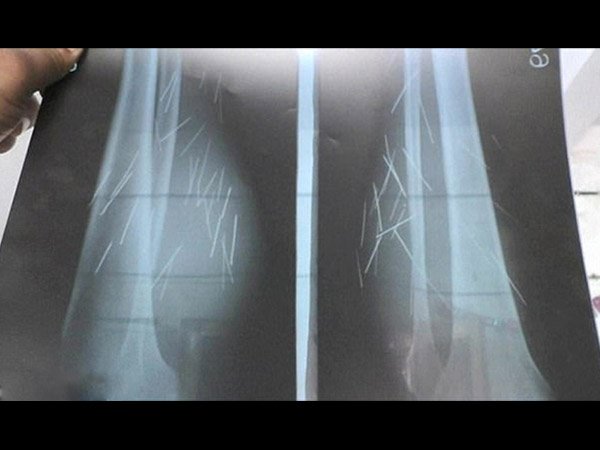

ಈ ಮಹಿಳೆಯ ಕಾಲಿನಿಂದ ಸೂಜಿ, ಸಿರಿಂಜಿನ ಮುಳ್ಳು, ಪಿನ್ನುಗಳು ಹೊರಬರುತ್ತಿವೆ!

ಭಾರತದಲ್ಲಿ ಓರ್ವ ಮಹಿಳೆ ತನ್ನ ಕಾಲಿನಿಂದ ಸೂಜಿಗಳು, ಸಿರಿಂಜಿನ ಮುಳ್ಳುಗಳು ಹಾಗೂ ಪಿನ್ನುಗಳು ನಿಯಮಿತವಾಗಿ ಹೊರಗೆ ಬರುತ್ತಿವೆ ಎಂದು ಹೇಳಿಕೊಂಡಿದ್ದಾಳೆ. ಈ ತೊಂದರೆ ತನಗೆ ಕೆಲವು ಕಾಲದಿಂದಲೂ ಇದ್ದು ತುಂಬಾ ತೊಂದರೆಯಾಗುತ್ತಿದೆ ಎಂದು ಹೇಳಿಕೊಂಡಿದ್ದಾಳೆ. ಆದರೆ ಕಾಲಿನಿಂದ ಸೂಜಿ ಹೊರಬರುವುದೆಂದರೆ? ಇದು ನೈಸರ್ಗಿಕವಂತೂ ಆಗಿರಲಿಕ್ಕಿಲ್ಲ.

ಅನುಸೂಯ್ಯಾ ದೇವಿ ಎಂಬ ಹೆಸರಿನ ಈ ಮಹಿಳೆ ಉತ್ತರಪ್ರದೇಶ ರಾಜ್ಯದ ಫತೆಹ್ ಪುರ್ ಜಿಲ್ಲೆಯ ಒಂದು ಪುಟ್ಟ ಗ್ರಾಮದ ನಿವಾಸಿಯಾಗಿದ್ದಾಳೆ. ಈಕೆ ತನ್ನ ಕಾಲಿನಿಂದ ಸೂಜಿಗಳು, ಸಿರಿಂಜುಗಳು ಹಾಗೂ ಪಿನ್ನುಗಳು ಹೊರಬರುವುದು 2012 ರಿಂದ ಪ್ರಾರಂಭವಾಯಿತು ಎಂದು ವಿವರಿಸಿದ್ದಾಳೆ.

ವೈದ್ಯರು ಇದೊಂದು ಮಾನಸಿಕ ರೋಗ ಎಂದು ಊಹಿಸುತ್ತಾರೆ. ಕೆಲವು ಸಂದರ್ಭಗಳಲ್ಲಿ ರೋಗಿ ತನಗೆ ಅರಿವೇ ಇಲ್ಲದಂತೆ ಕೆಲವು ಮೊನಚಾದ ವಸ್ತುಗಳನ್ನು ತನ್ನ ದೇಹದೊಳಗೆ ತೂರಿಸಿಕೊಳ್ಳುವುದು ಒಂದು ಮಾನಸಿಕ ವ್ಯಾಧಿಯ ಲಕ್ಷಣವಾಗಿದೆ. ಈ ಮಹಿಳೆಯೂ ಇಂತಹ ಯಾವುದೋ ಮಾನಸಿಕ ವ್ಯಾಧಿಗೆ ತುತ್ತಾಗಿದ್ದು ತನಗರಿವಿಲ್ಲದಂತೆಯೇ ಚೂಪಾದ ವಸ್ತುಗಳನ್ನು ತನ್ನ ಕಾಲುಗಳ ಒಳಗೆ ಚುಚ್ಚಿಕೊಳ್ಳುತ್ತಿದ್ದರಬಹುದು. ಆದರೆ ಈ ಆರೋಪವನ್ನು ಅನುಸೂಯ್ಯಾ ಸ್ಪಷ್ಟವಾಗಿ ತಳ್ಳಿ ಹಾಕಿ ತನಗಾವುದೇ ರೋಗವಿಲ್ಲ ಹಾಗೂ ತಾನು ತನ್ನ ಕಾಲುಗಳಿಗೆ ಚುಚ್ಚಿಕೊಂಡಿಲ್ಲ ಎಂದೇ ವಾದಿಸುತ್ತಾಳೆ.

ಮೂಲಗಳ ಪ್ರಕಾರ ಈಕೆಯ ಶರೀರದಿಂದ ಮೂರು ಬಗೆಯ ಚೂಪಾದ ವಸ್ತುಗಳು ಹೊರಬರುತ್ತಿವೆ. ಇವೆಂದರೆ ಬಟ್ಟೆ ಹೊಲಿಯುವ ದಾರದ ಸೂಜಿಗಳು, ಆಸ್ಪತ್ರೆಯಲ್ಲಿ ಚುಚ್ಚುಮದ್ದು ನೀಡಲು ಬಳಸುವ ಸಿರಿಂಜಿನ ಸೂಜಿ ಹಾಗೂ ಮೊಳೆಗಳು. ದೇಹದಲ್ಲಿ ಇವನ್ನು ಉತ್ಪಾದಿಸುವ ಯಾವುದೇ ವ್ಯವಸ್ಥೆ ಇಲ್ಲದೇ ಇರುವ ಕಾರಣ ಸ್ಪಷ್ಟವಾಗಿ ಇವು ದೇಹದೊಳಗೆ ತೂರಿಸಲ್ಪಟ್ಟಿರಬೇಕು. ಅಷ್ಟಕ್ಕೂ ಸಿರಿಂಜಿನ ಸೂಜಿ ದಪ್ಪನಾಗಿದ್ದು ಇದು ದೇಹದೊಳಗೆ ತೂರಿಕೊಳ್ಳಲು ಹೇಗಾದರೂ ಸಾಧ್ಯವಾಯಿತು ಎಂದು ಅಚ್ಚರಿಯಾಗುತ್ತದೆ.

ಈ ಬಗ್ಗೆ ಈಕೆ ನೀಡುವ ವಿವರಣೆಯಂತೆ ಮೊದಲು ಚರ್ಮದ ಯಾವುದೋ ಒಂದು ಭಾಗದಲ್ಲಿ ಚಿಕ್ಕ ಮೊಡವೆಯೊಂದು ಮೂಡುತ್ತದೆ. ಕೆಲದಿನಗಳ ಬಳಿಕ ಇದು ಸಾಕಷ್ಟು ದೊಡ್ಡದಾಗಿ ಬಳಿಕ ಸಿಡಿದು ಒಡೆಯುತ್ತದೆ. ಸಿಡಿಯುವ ಸಮಯದಲ್ಲಿ ಮೊಡವೆಯೊಳಗೆ ಸಂಗ್ರಹವಾಗಿದ್ದ ಕೀವು ಸಹಾ ಹೊರಚೆಲ್ಲಲ್ಪಟ್ಟು ಇದರೊಂದಿಗೇ ಸೂಜಿ ಅಥವಾ ಮೊಳೆಯೊಂದು ಹೊರಬೀಳುತ್ತದೆ. ಇದು ಕೇಳಲು ಅಥವಾ ನೋಡಲು ಕಷ್ಟಕರವಾದರೂ ಇದು ತನ್ನಿಂತಾನೇ ಆಗಲು ಸಾಧ್ಯವಿಲ್ಲ ಎಂದೇ

ವೈದ್ಯರು ತಿಳಿಸುತ್ತಾರೆ. ನಮ್ಮ ದೇಹ ಮೊಳೆ, ಸೂಜಿಗಳನ್ನು ಸೃಷ್ಟಿಸಲಾರದು. ಅದೂ ಅಲ್ಲದೇ ಸ್ಪಷ್ಟವಾದ ಮಾನವನಿರ್ಮಿತ ಆಕಾರದ ಸೂಜಿ ಮೊಳೆಗಳನ್ನು ಮಾನವ ದೇಹ ಹೇಗೆ ನಿರ್ಮಿಸಲು ಸಾಧ್ಯ?